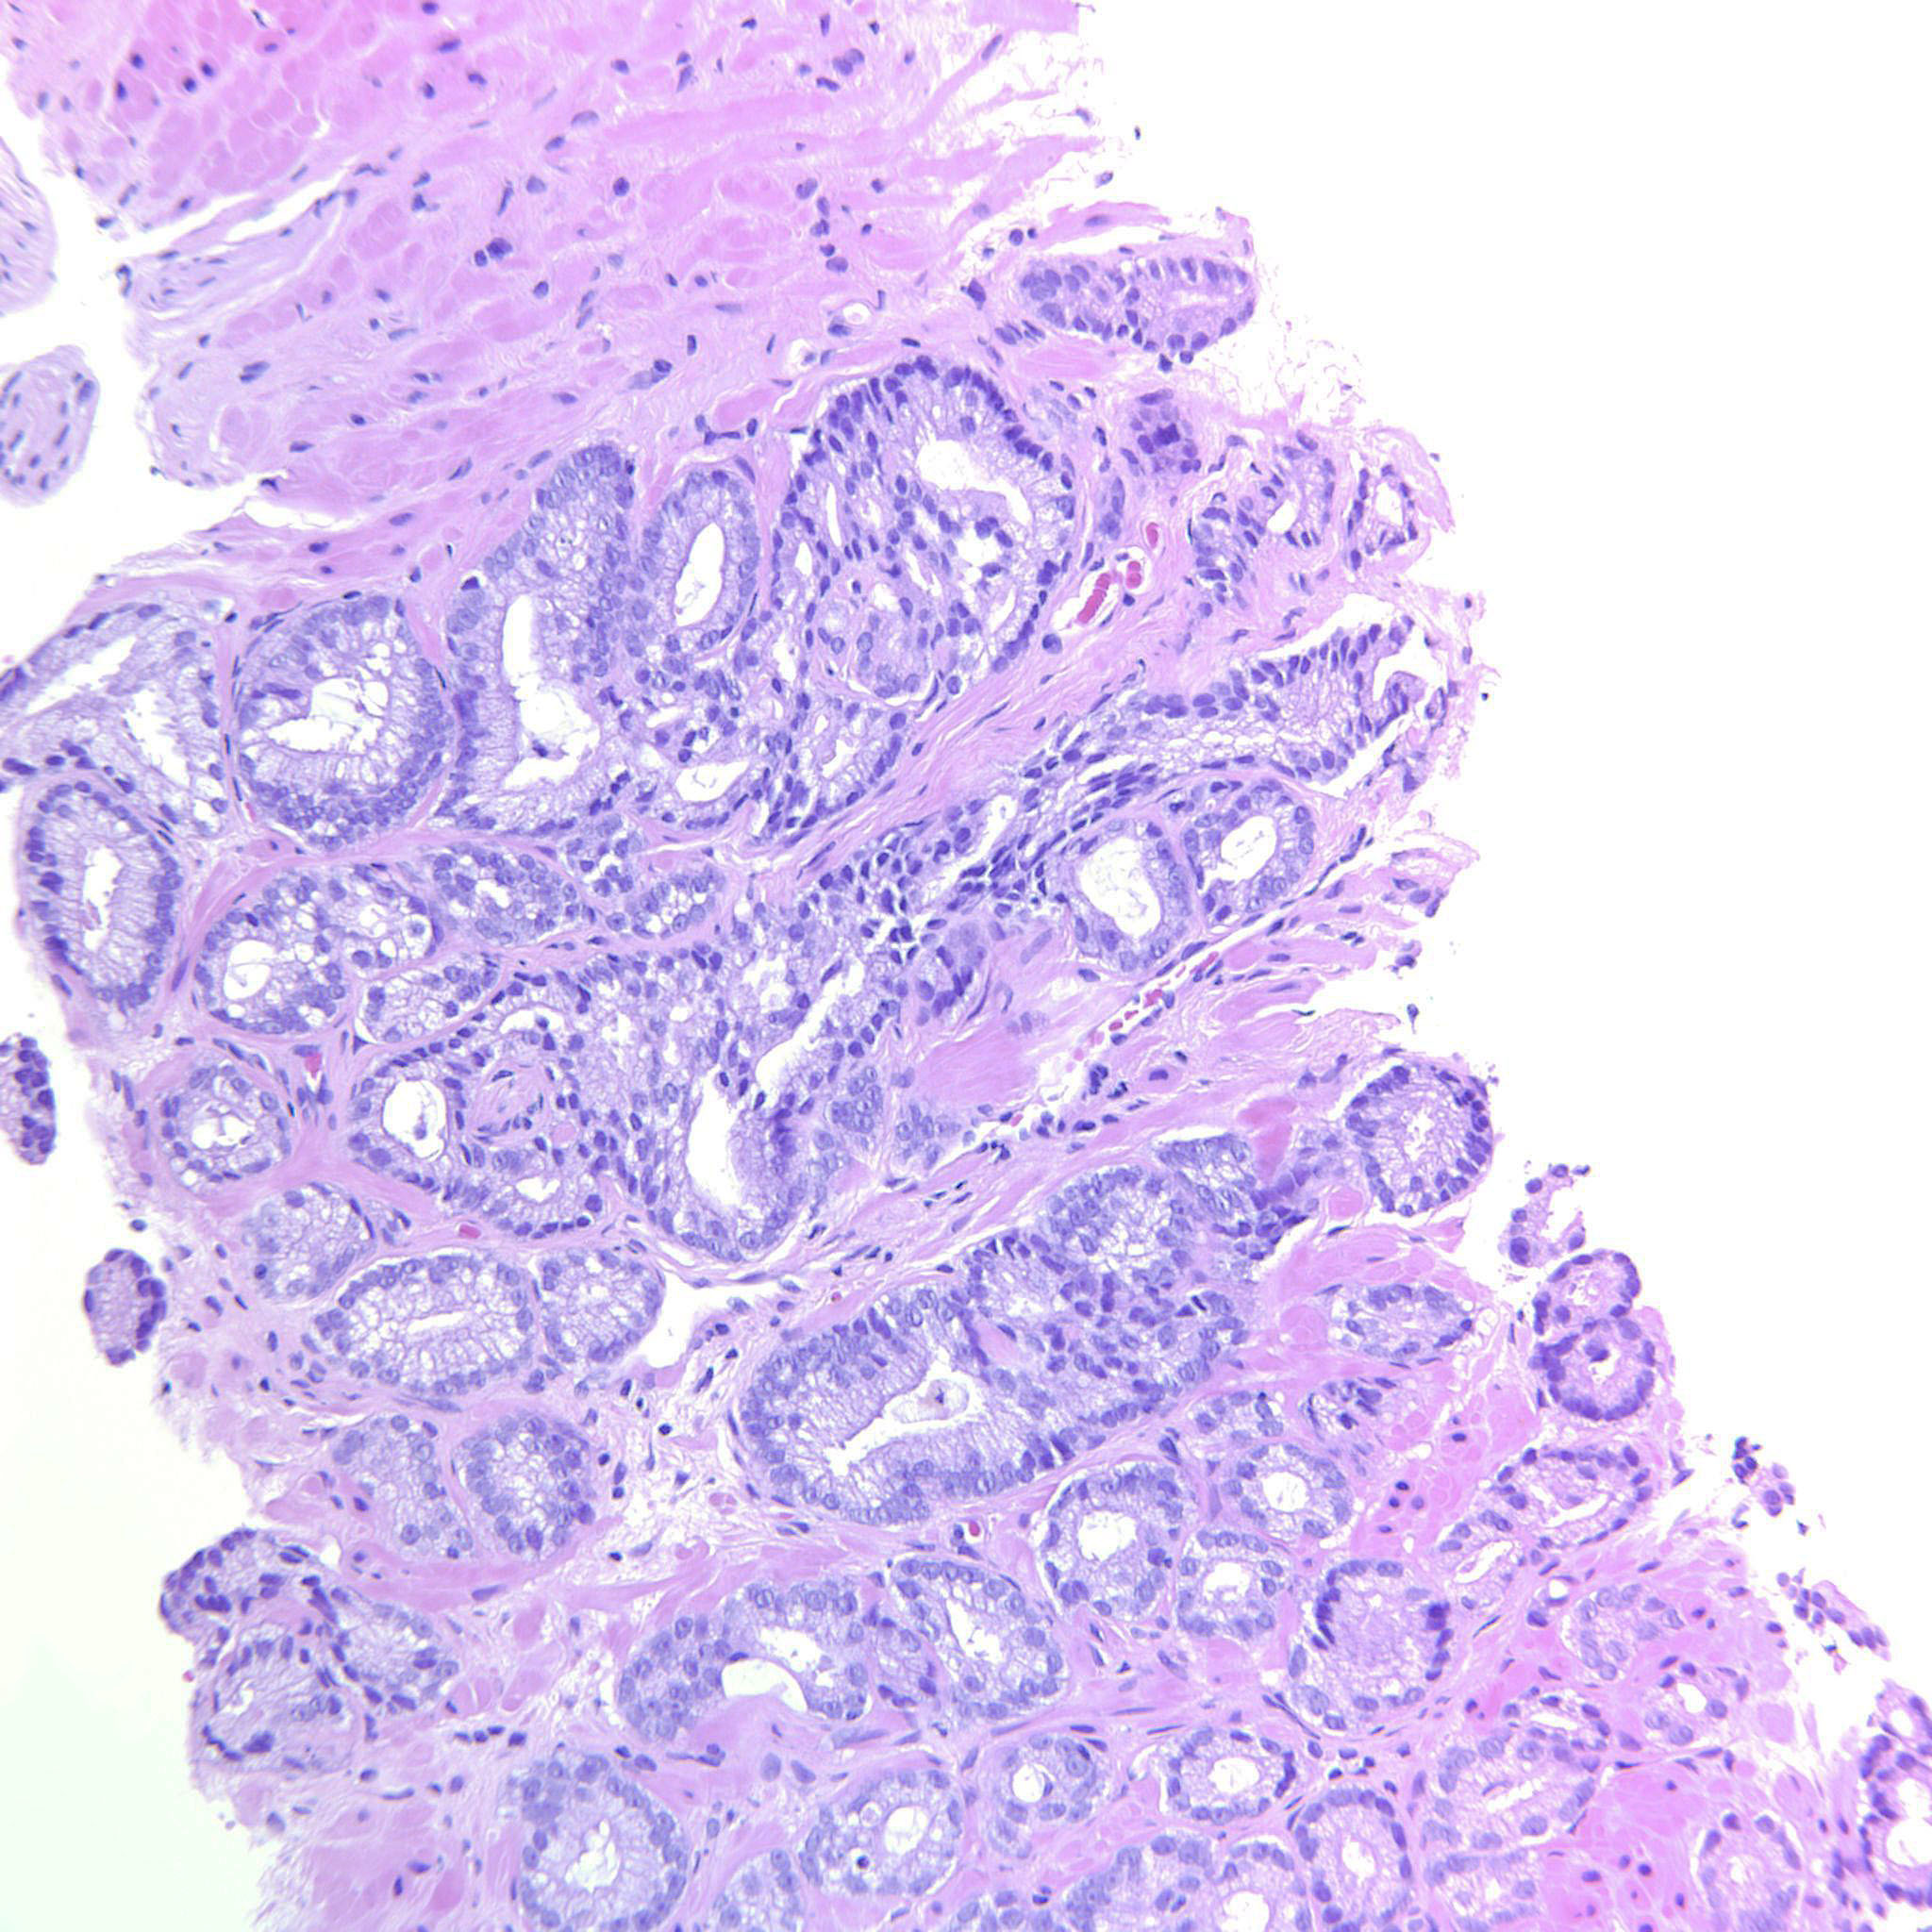

Consensus grade: GS 3+4=7 (ISUP 2)

Case description (by case creator):

Scattered poorly formed glands throughout the material.